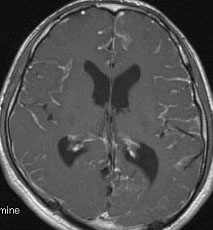

水頭症とけいれん発作で発症した例

年長児例でけいれん発作と水頭症で発症した子どもです。中央の画像に見えるように,脳幹部の周囲が線状に白く増強されています。頭頂部にはゴロンとした腫瘤形成があり,これは悪性黒色腫 メラノーマだと考えられます。